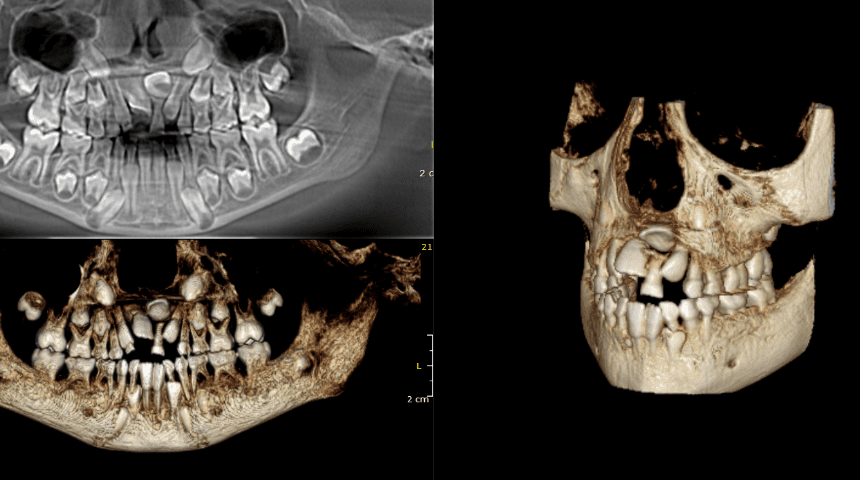

La tomografía dental completa, también conocida como tomografía computarizada de haz cónico (CBCT por sus siglas en inglés), es una técnica de imagenología avanzada utilizada en odontología para obtener imágenes detalladas de la estructura dental y ósea. A diferencia de las radiografías dentales tradicionales, que proporcionan imágenes bidimensionales, la tomografía dental completa ofrece una vista tridimensional del área de interés.

- Visualización precisa de estructuras óseas: Permite a los dentistas ver el hueso de la mandíbula, los senos maxilares y otras estructuras óseas con gran detalle, lo que es útil para planificar tratamientos quirúrgicos y la colocación de implantes dentales.

- Evaluación de la calidad ósea: Facilita la evaluación de la densidad y la calidad del hueso, crucial para el éxito de tratamientos como los implantes dentales.

- Detección de anomalías: Ayuda a identificar problemas como quistes, tumores, infecciones o problemas en la estructura dental que podrían no ser evidentes con radiografías convencionales.

- Planificación de tratamientos: Permite una planificación más precisa para tratamientos complejos, como la cirugía ortognática o la colocación de implantes, al ofrecer una visión detallada del entorno tridimensional.

- El paciente se coloca en una máquina de tomografía que gira alrededor de la cabeza, tomando múltiples imágenes desde diferentes ángulos. Estas imágenes se procesan por computadora para crear un modelo 3D de la zona a examinar. El procedimiento suele ser rápido y no invasivo, con una exposición a la radiación menor que la de una tomografía computarizada convencional.

- Preparen un tratamiento de ortodoncia: La tomografía 3D permite a los ortodoncistas evaluar la posición de los dientes y la estructura ósea del maxilar inferior para planificar un tratamiento de ortodoncia más preciso.

- Necesiten una cirugía oral: La tomografía 3D permite a los cirujanos orales planificar la cirugía con mayor precisión, minimizando los riesgos y mejorando los resultados.